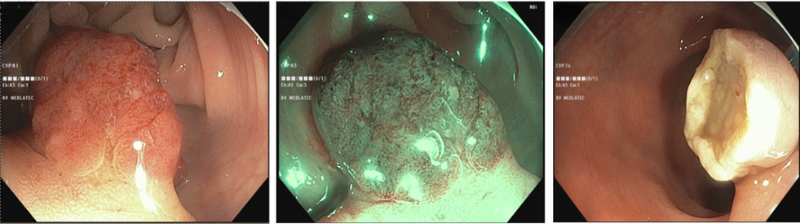

Hình ảnh polyp tại đại tràng sigma và trực tràng

Trên nội soi đại tràng phát hiện có vài polyp ở đại tràng sigma và trực tràng. Trong đó, polyp ở đại tràng sigma có kích thước khá lớn (khoảng 2cm), đầu polyp có vùng biến đổi cấu trúc hoàn toàn, phân loại NICE 2.